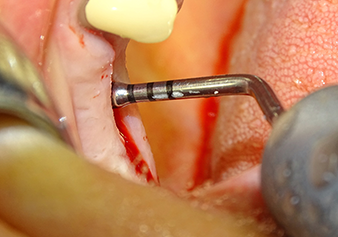

Lo strumento I2A (diametro 2,0 mm) è stato quindi impiegato per perforare il pavimento sinusale in modo graduale e su superfici molto ridotte. Tale metodo piezochirurgico previene il danneggiamento della membrana di Schneider. Durante l'utilizzo di Z25P, la membrana risultava già essere leggermente sollevata dal fluido di raffreddamento fornito attraverso la punta dello strumento (Fig. 3). La quantità di fluido di raffreddamento presente era solo del 50% per evitare che la sede dell'impianto registrasse un'elevata pressione.